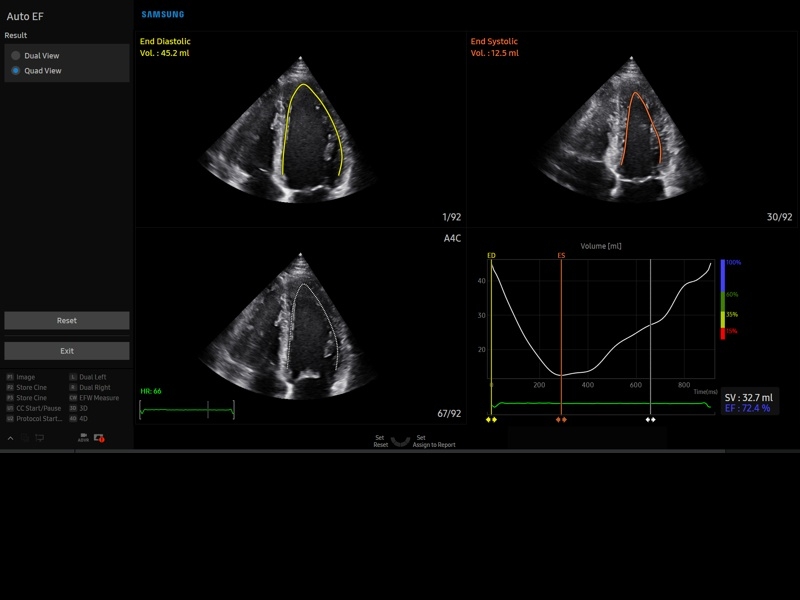

• МодульStrain+- программа не векторной оценки степени сократимости миокарда с выведением автоматически расчетов и графиков на экране отдельно по каждому сегменту.

• Пакет кардиологических исследований.

М-режим:измерение диаметра аорты, передне-заднего размера ЛП, толщины МЖП (систолическая и диастолическая), толщины ЗСЛЖ (систолическая и диастолическая), размеров ЛЖ и ПЖ (систолический и диастолический), ФВ (Teichholz).

B-режим:измерение диаметра аорты (восходящей, дуги, нисходящей, на уровне синусов Вальсальвы, на уровне створок аортального клапана), определение размеров ЛП и ПП (максимальный, минимальный, систолический, диастолический, переднее-задний, верхнее-нижний, медиально-латеральный), расчет объемов ЛП и ПП, объемов ЛЖ (метод "Площадь-Длина", метод дисков (Simpson)), массы миокарда ЛЖ, индекса массы миокарда ЛЖ.